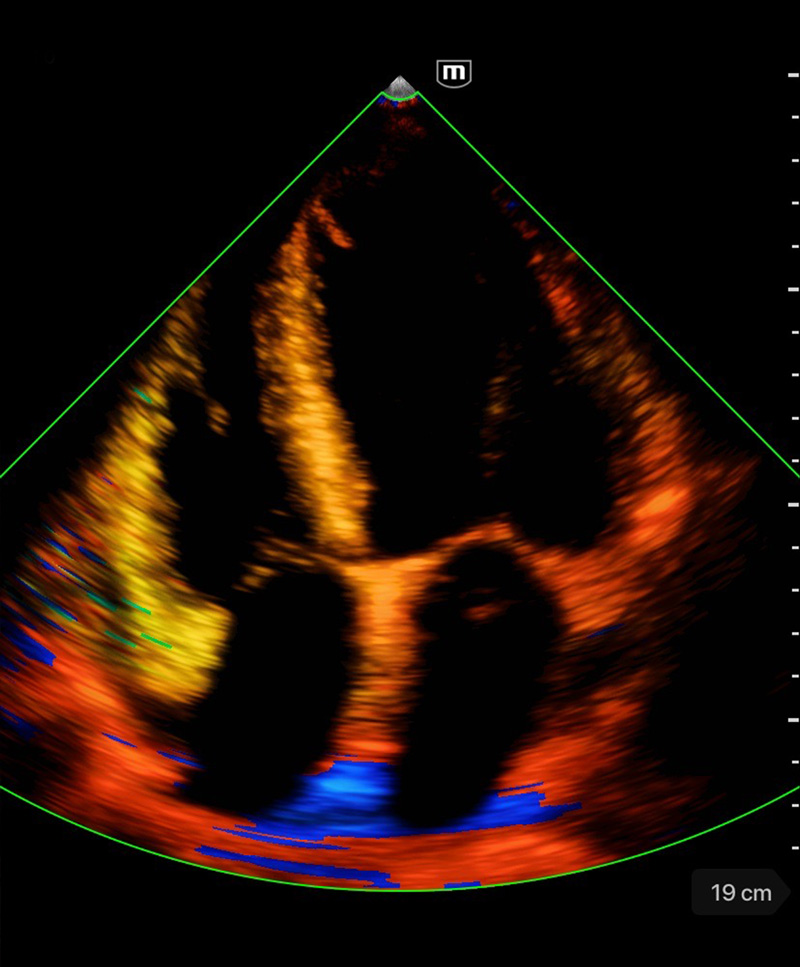

Множество режими за сканиране

Color mode

Кардиология

Бърза диагностика на сърдечната функция; скрининг за сърдечна патология

Клинични снимки